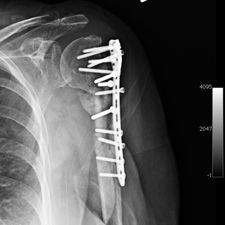

Ms. Q, age 74, initially presented on December 10, 2009, following a multiply comminuted, osteoporotic fracture of her left proximal Humerus. The decision was made to do an ORIF, which was carried out on December 14, 2009. She had a locking plate implanted following which she developed an infection of the wound. She was initially treated with antibiotics for this and she continued to get some oozing of the wound, which did not settle down despite continued use of the various antibiotics including Augmentin. Multiple wound swabs were done which failed to grow any organisms. The oozing persisted until about eight weeks following her operation when it finally settled down and the scar was noted to be tethered and was thought to be tethered onto bone.

She continued to have problems with intermittent cellulitis and pain in the arm and the decision was made to do an early removal of the metal work. This was carried out in mid March 2010 and at operation, which was done through the original incision and anterior extended deltopectoral approach, she was noted to have healed the fracture. She did well postop and was continuing to mobilize.